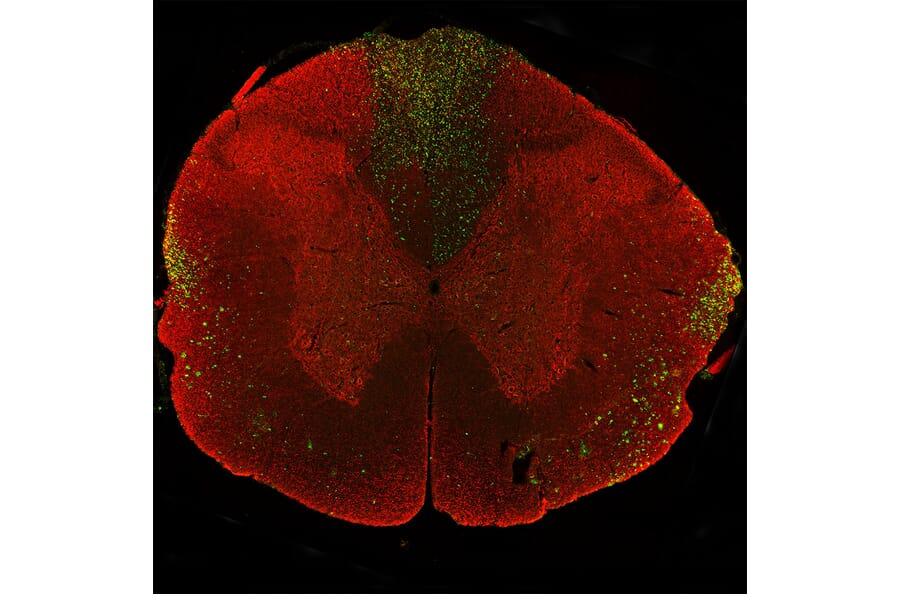

Immunostaining of a coronal section of the spinal cord of a rat given a midline C4 contusion injury three days previously. Sections were stained with Anti-NF-L Antibody (A270580) (red) and Anti-NF-L Antibody [6H63] (A333276) (green). Anti-NF-L Antibody [6H63] (A333276) stains prominent aggregates of material concentrated in the lateral funiculi and the dorsal columns but seen in lesser amounts throughout the section. These are degenerating and degenerated axons damaged by the C4 lesion. The Anti-NF-L Antibody antibody binds the C-terminal “tail” region of NF-L which is absent or destroyed during degeneration, so the positive profiles are largely negative for Anti-NF-L Antibody.